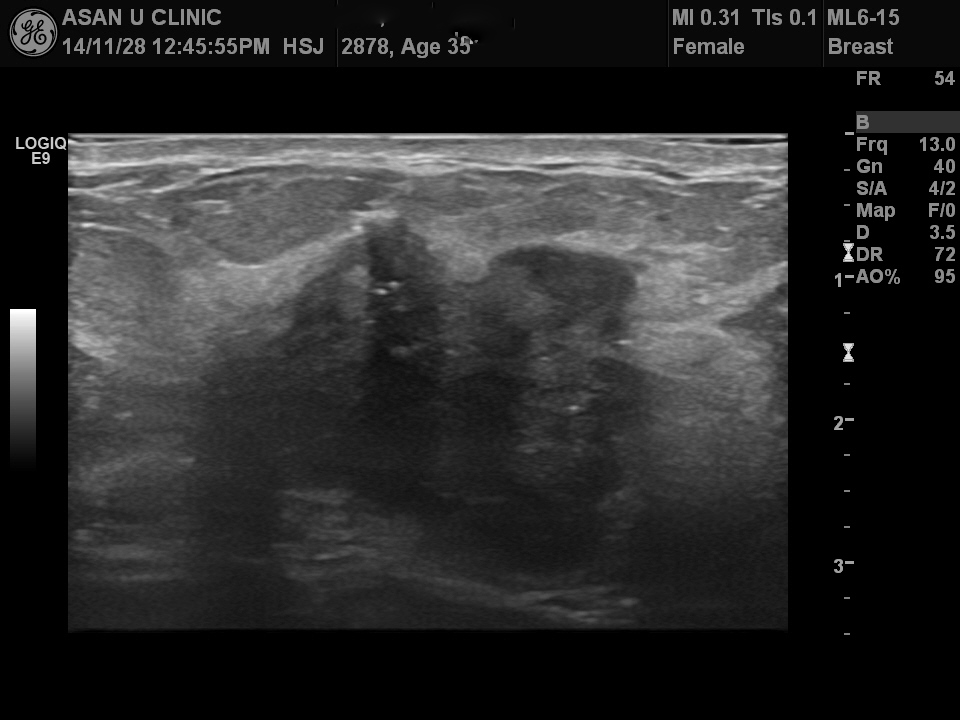

한달전부터 우측 유방에 멍우리가 만져지는데 없어지지 않아 내원한 35세 여성분입니다.

초음파상 내부에 미세석회화가 불규칙하게 있으며 경계가 좋지 않은 모먕을 가져

조직검사를 시행하였습니다.

조직검사상 침윤성 유관암으로 진단되었습니다.